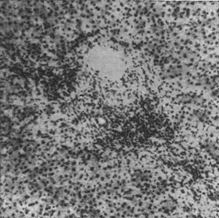

Рассеянные очаги некроза печеночных клеток и усиленная пролиферация внутридольковых мезенхимальных клеток обусловливают выраженное в большей или меньшей степени нарушение балочного строения и диссоциацию печеночных клеток или комплексов их (рис. 1 и отд. табл., рис. 3).

Во II фазе — разгар заболевания (желтушный период) — количество клеточных инфильтратов в портальных полях увеличивается, они содержат примесь плазматических клеток и сегментоядерных лейкоцитов, располагаются то диффузно, то перилобулярно вокруг желчных прекапилляров (холангиол), то вокруг вен или желчных протоков портальной триады. (см. отд. табл., рис. 2). Разрыхление стромы, отек и инфильтраты могут распространиться и на стенку желчного пузыря, особенно на его ложе (процессы, которые возникают иногда еще в преджелтушном периоде заболевания). Некрозы эпителиальных клеток нарастают, могут сосредоточиться в центрах долек, обусловливая разрежение их. Значительно нарастают процессы регенерации печеночных клеток, причем митотическое деление сменяется амитотическим. Помимо внутридольковой, отмечается регенерация и по периферии долек в виде пролиферирующих холангиол. Увеличиваются и внутридольковые клеточные инфильтраты. Некоторые желчные капилляры заполняются желчными тромбами, чему соответствуют клинически выраженные признаки механической желтухи. В этой фазе отмечается некоторое огрубение стромы: пролиферация и коллагенизация аргирофильных волокон как внутри дольки, так и по ее периферии.

В III фазе (период выздоровления) перипортальные инфильтраты уменьшаются, убывает количество некротизированных печеночных клеток, нарастают процессы амитотического деления клеток. Внутрпдольковая пролиферация мезенхимальных клеток стихает, становится более очаговой и узелковой.

Еще некоторое время после клинического выздоровления о незаконченности процессов восстановления свидетельствуют: лимфогистиоцитарные инфильтраты в портальной зоне (рис. 2), полиморфизм печеночных клеток, обилие многоядерных печеночных клеток, наличие липофусцина, а иногда и железосодержащего пигмента в ретикулярных клетках и наличие желчных тромбов в отдельных желчных капиллярах. Спустя более или менее длительный период (3—4 мес.) после перенесенной Б. б., наступает либо полное морфологическое восстановление, либо обнаруживаются остаточные изменения, выражающиеся в очаговом, портальном или центральном фиброзе; последний, как показывают исследования сериальных пункционных биопсий печени, с течением времени иногда полностыо исчезает. Интенсивность описанных воспалительных, некротических и регенеративных процессов может значительно варьировать: в некоторых случаях легкого течения II фаза полностью выпадает, и I фаза непосредственно переходит в III. Морфологические изменения печени при желтушной и безжелтушной формах Б. б. при инфекционном гепатите (спонтанном) и при сывороточном (шприцевом) одинаковы. Морфологические изменения печени при рецидивах Б. б. и повторных заболеваниях аналогичны изменениям при острой форме.